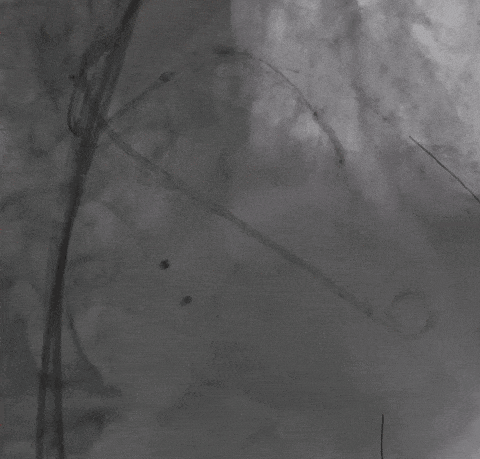

Step 5 左主干植入支架 回旋支开口予以切割+药物球囊